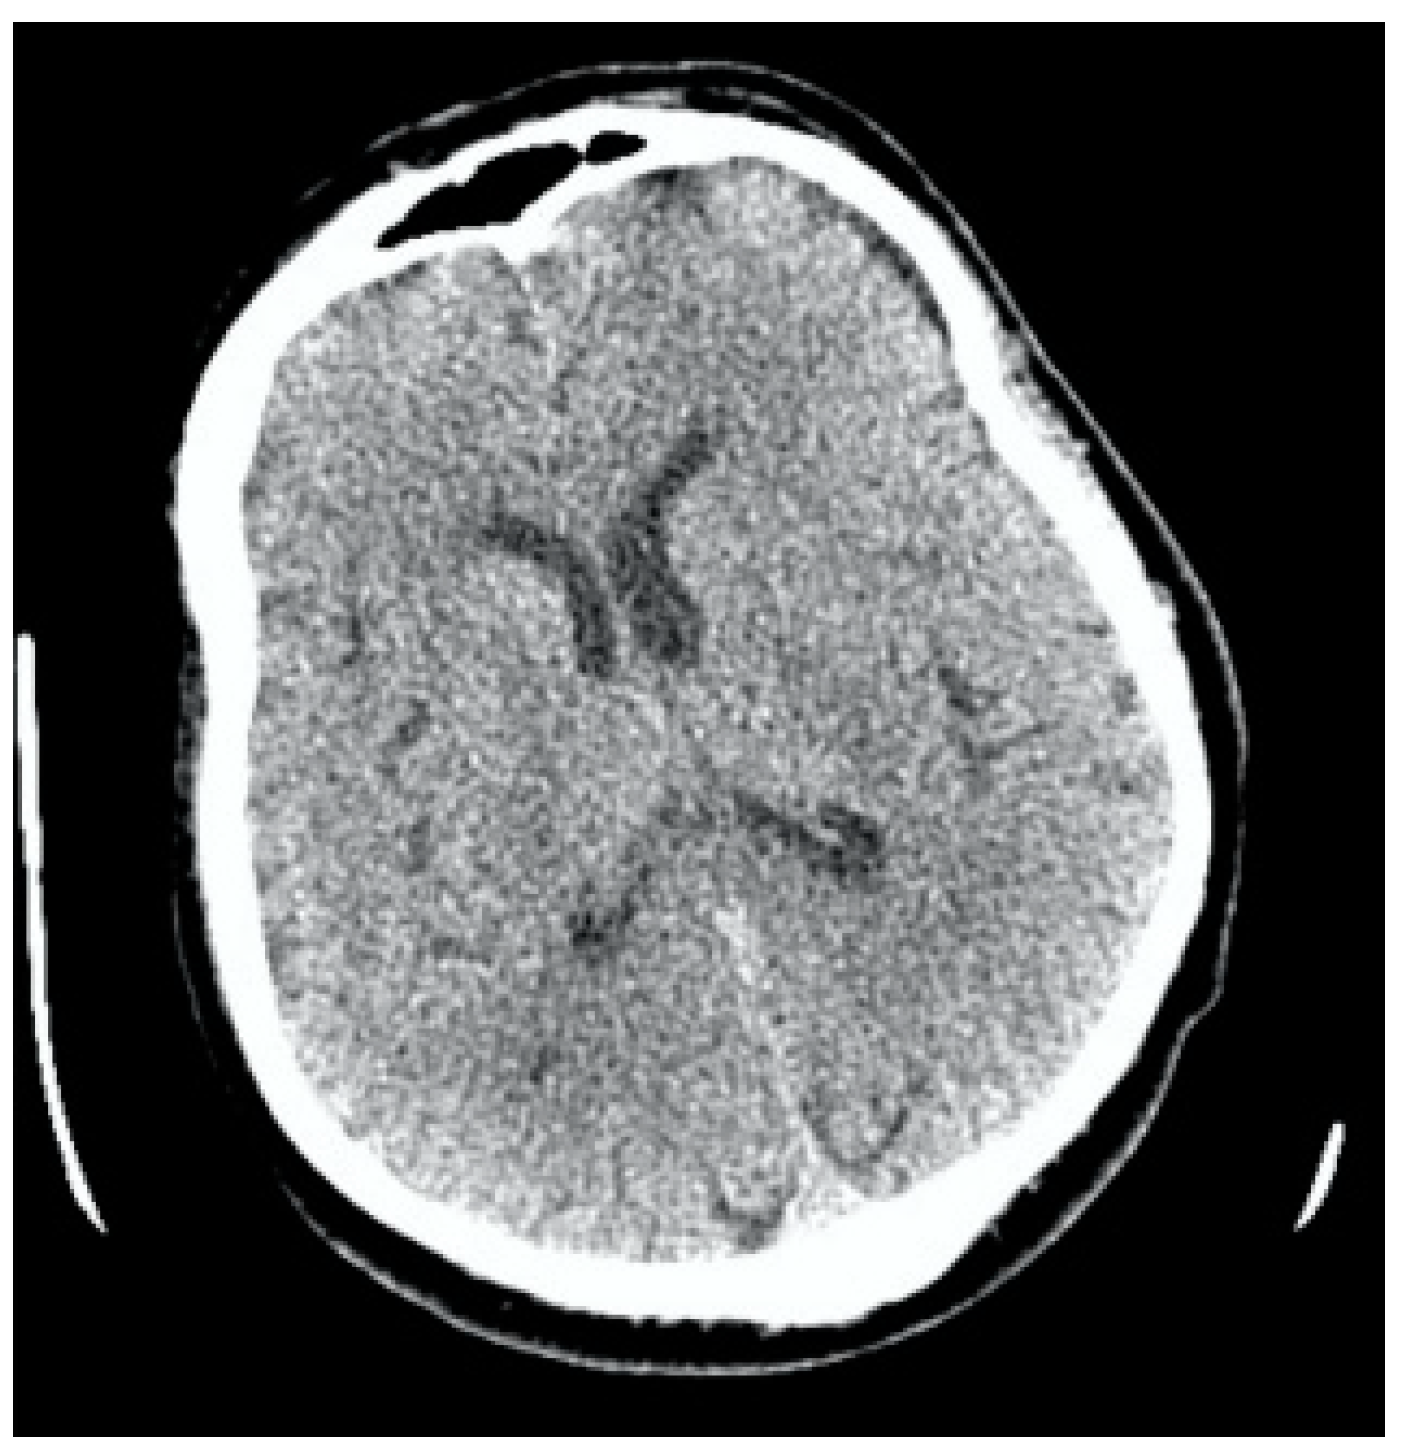

Clinical Case 2. Patient S., a 60-year-old male, was hospitalized by ambulance from a public place (pharmacy). At the time of admission, the blood pressure was 210/130 mm Hg. The patient had right-sided hemiplegia, smoothness of the nasolabial fold, motor aphasia, and showed 14 points on the NIH scale. The hypertension correction was made by the intravenous administration of Urapidil at a dosage of 10 mg. The patient got an emergency MSCT, which showed the absence of ischemic changes on the ASPECTS scale of 10 points (Figure 9).

Figure 9.

Clinical Case 2, Patient S., male, 60 years old. Cerebral MSCT in 30 min after the onset of symptoms. There are no data for ischemia and brain damage, ASPECTS = 10.

The visual assessment of the right lower limb showed the pallor of the skin. According to an ultrasound examination, the blood flow through the superficial femoral artery was slowed down. The decision on surgical aorta prosthetics was also postponed until the assessment of brain damage. The neurological deficit according to the NIH scale at the end of revascularization remained at 29 points; according to the Glasgow Coma Scale, it was 7 points. A repeated CT performed in 24 h showed severe cerebral edema and ischemic brain damage. ASPECT = 2 (Figure 14).

Figure 14.

Clinical Case 2, Patient S., male, 60 years old. MSCT angiography in 24 h after revascularization. (A) Brain edema of both hemispheres was determined; (B) MSCT aortography showed the type A aortic dissection; (C) circulation through the cerebral arteries is preserved; (D) circulation in the right lower limb is preserved.